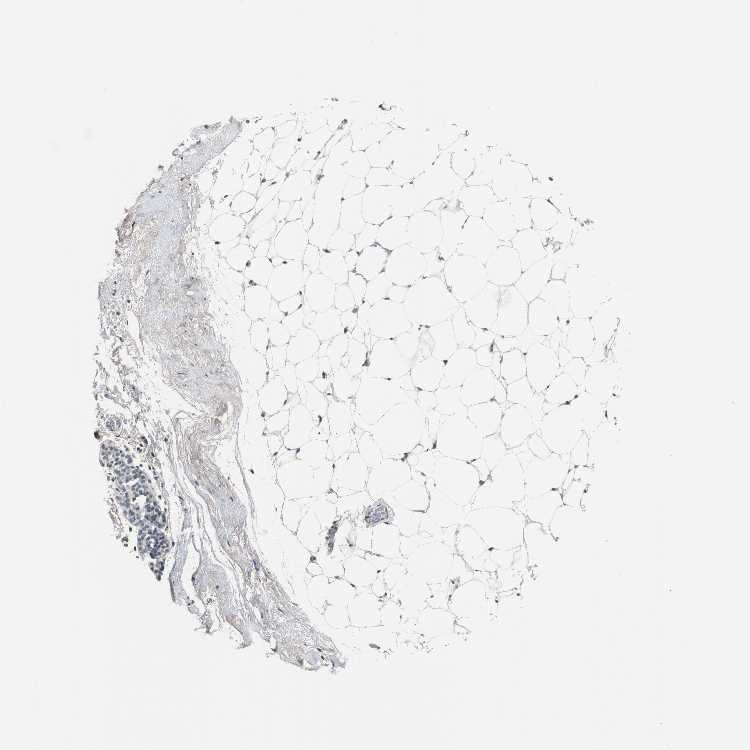

BREAST - Antibody stainingi

Antibody staining in the annotated cell types in the current human tissue is reported as not detected, low, medium, or high, based on conventional immunohistochemistry profiling in selected tissues. This score is based on the combination of the staining intensity and fraction of stained cells.

Each image is clickable and will lead to virtual microscopy that enables deeper exploration of all samples and also displays staining intensity scores, fraction scores and subcellular localization as well as patient and tissue information for each sample.

Antibody HPA006458Antibody HPA026773Antibody CAB002448

Adipocytes LowNot detectedNot detected

Glandular cells MediumNot detectedLow

Myoepithelial cells Not detectedLowNot detected